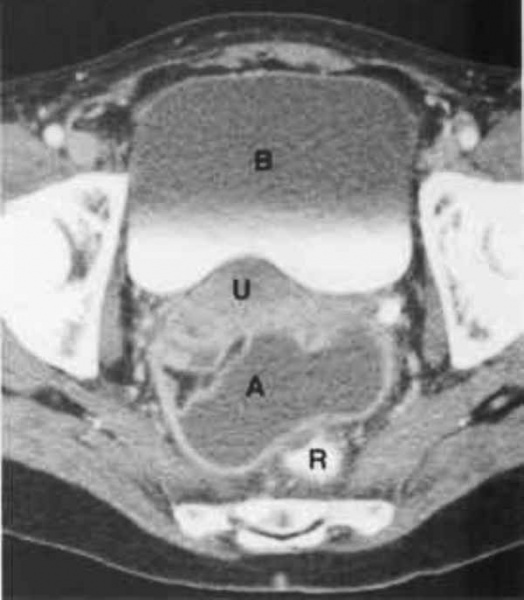

КТ-исследование абсцесса малого таза: Визуализация и диагностика

Раздел: Фотоальбом решений